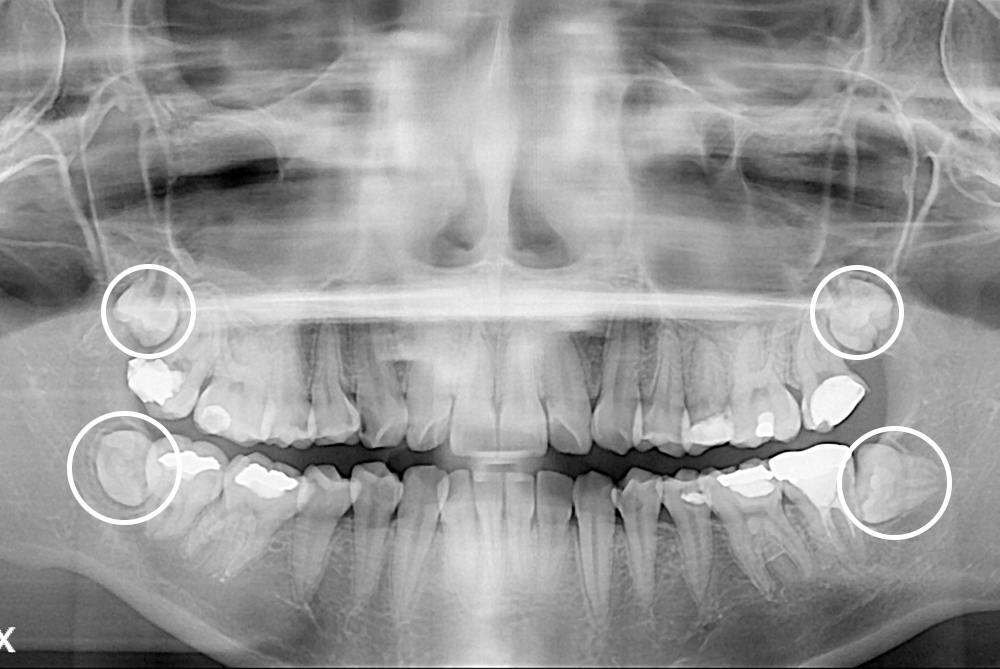

[사랑니] 매복 사랑니 발치

치료후 : 2017-01-14

세종치과는 구강악안면외과학 박사이신 원장님이 발치하는 치과입니다.